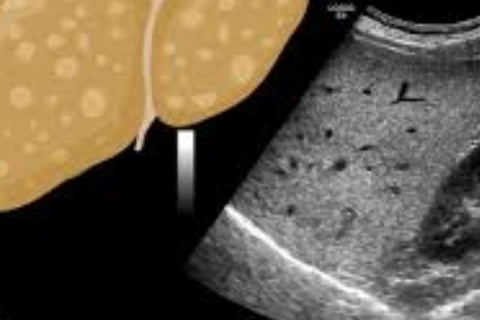

الكبد الدهني من الدرجة الأولى: يعتبر حالة خفيفة حيث تشكل الدهون 5-10% من الكبد. من المهم تناول طعام صحي وممارسة الرياضة بانتظام.

الكبد الدهني من الدرجة الثانية: يحدث عندما تتراوح نسبة الدهون في الكبد بين 10-25%.

الكبد الدهني من الدرجة الثالثة: هو الأكثر خطورة، حيث يشير إلى نسبة مرتفعة من الدهون في الكبد مع التهاب في الأنسجة المحيطة.

يمكن أن يحدث هذا في كل من الكبد الدهني غير الكحولي والكبد الدهني الكحولي، وتزيد مخاطر الإصابة بالكبد الدهني من الدرجة الثالثة مع السمنة ومرض السكري من النوع 2 ومتلازمة التمثيل الغذائي.

يتم تصنيف مرض الكبد الدهني إلى درجات مختلفة بناءً على نسبة الدهون المتراكمة في الكبد.

الدرجة الأولى هي حالة خفيفة حيث تشكل الدهون 5-10% من الكبد، ويمكن إدارتها من خلال النظام الغذائي والتمارين الرياضية.

الدرجة الثانية تعني تراكم الدهون بنسبة 10-25% من الكبد.

الدرجة الثالثة هي الأكثر خطورة حيث يكون هناك تراكم كبير للدهون والالتهابات في الكبد والمناطق المحيطة.